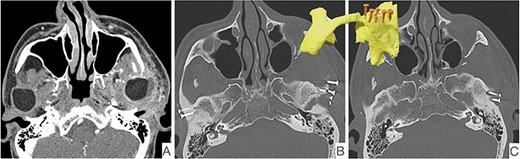

This report is about a 63-year-old patient suffering of bilateral deforming TMJ arthrosis (Wilkes-V) from a bilateral condylar fracture. In 2019 he presented himself to the Department of Oral and Maxillofacial Surgery, showing painful palpation above both TMJs and a severely decreased mouth opening (maximum interincisal distance of 1.5 cm). A computed tomography (CT) scan then revealed pathognomonic changes with flattening of the condyle and articular eminentia as well as partial ankylosis of the right TMJ (Fig. 1). Based on these findings, we decided for a bilateral TMJ-TJR. At this point, the patient only wanted one side replaced for the time being. After impressions were taken, plaster models were 3D-surface scanned and in combination with the CT dataset further processed by Zimmer-BiometTM (Warsaw, USA) for patient-specific TJR (PSI-TJR) fabrication. Another 3 months later, the TMJ-TJR of the right side could be carried out (Fig. 2). Postoperatively the patient received antibiotics for overall 7 days. Satisfied with the result, the patient requested reconstruction of the left TMJ 6 months later. With an improved mouth opening (2.8 cm), impressions were taken using an intraoral scanner. After PSI fabrication, the operation was carried out 9 months after (Fig. 3). Six weeks following surgery, the patient presented with a painful preauricular swelling on the left side, which was diagnosed as aseptic inflammation in the absence of erythema and pathologic joint puncture. Showing a periarticular edema, a broken screw and radial osteolysis around the drilling channels, a subsequent CT scan indicated the loosening of the ultra-high-molecular-weight-polyethylene (UHMWPE) fossa component (Fig. 4). In view of the long production time of new custom-made components and the damaged implant site, we decided to explant the fossa and to temporarily replace it with a non-fixed patient-specific spacer made of COPAL®-bone-cement (Fig. 5) (gentamicin and clindamycin additive) (Haereus; Hanau, Germany). The workflow included the surface scan of the original fossa-drilling template, the computer-aided design of a two-part press mould and the intraoperative fossa fabrication from COPAL®-bone-cement. With the use of a rubber elastic intermaxillary fixation, the vertical mandibular relation could be secured, painful movements and muscle shortening avoided and the risk of perioperative infection could be sufficiently minimized (Fig. 6). After 3 months without complications, the patient-specific COPAL® component could be removed and the new patient-specific UHMWPE fossa inserted within sufficiently regenerated bone (Fig. 7).

CT scan showing radiological signs of loosening of the left fossa component. On the left, the presentation of the periprosthetic edema (A), fracture of an osteosynthesis screw (B) and the osteolysis around the screw shafts (C).